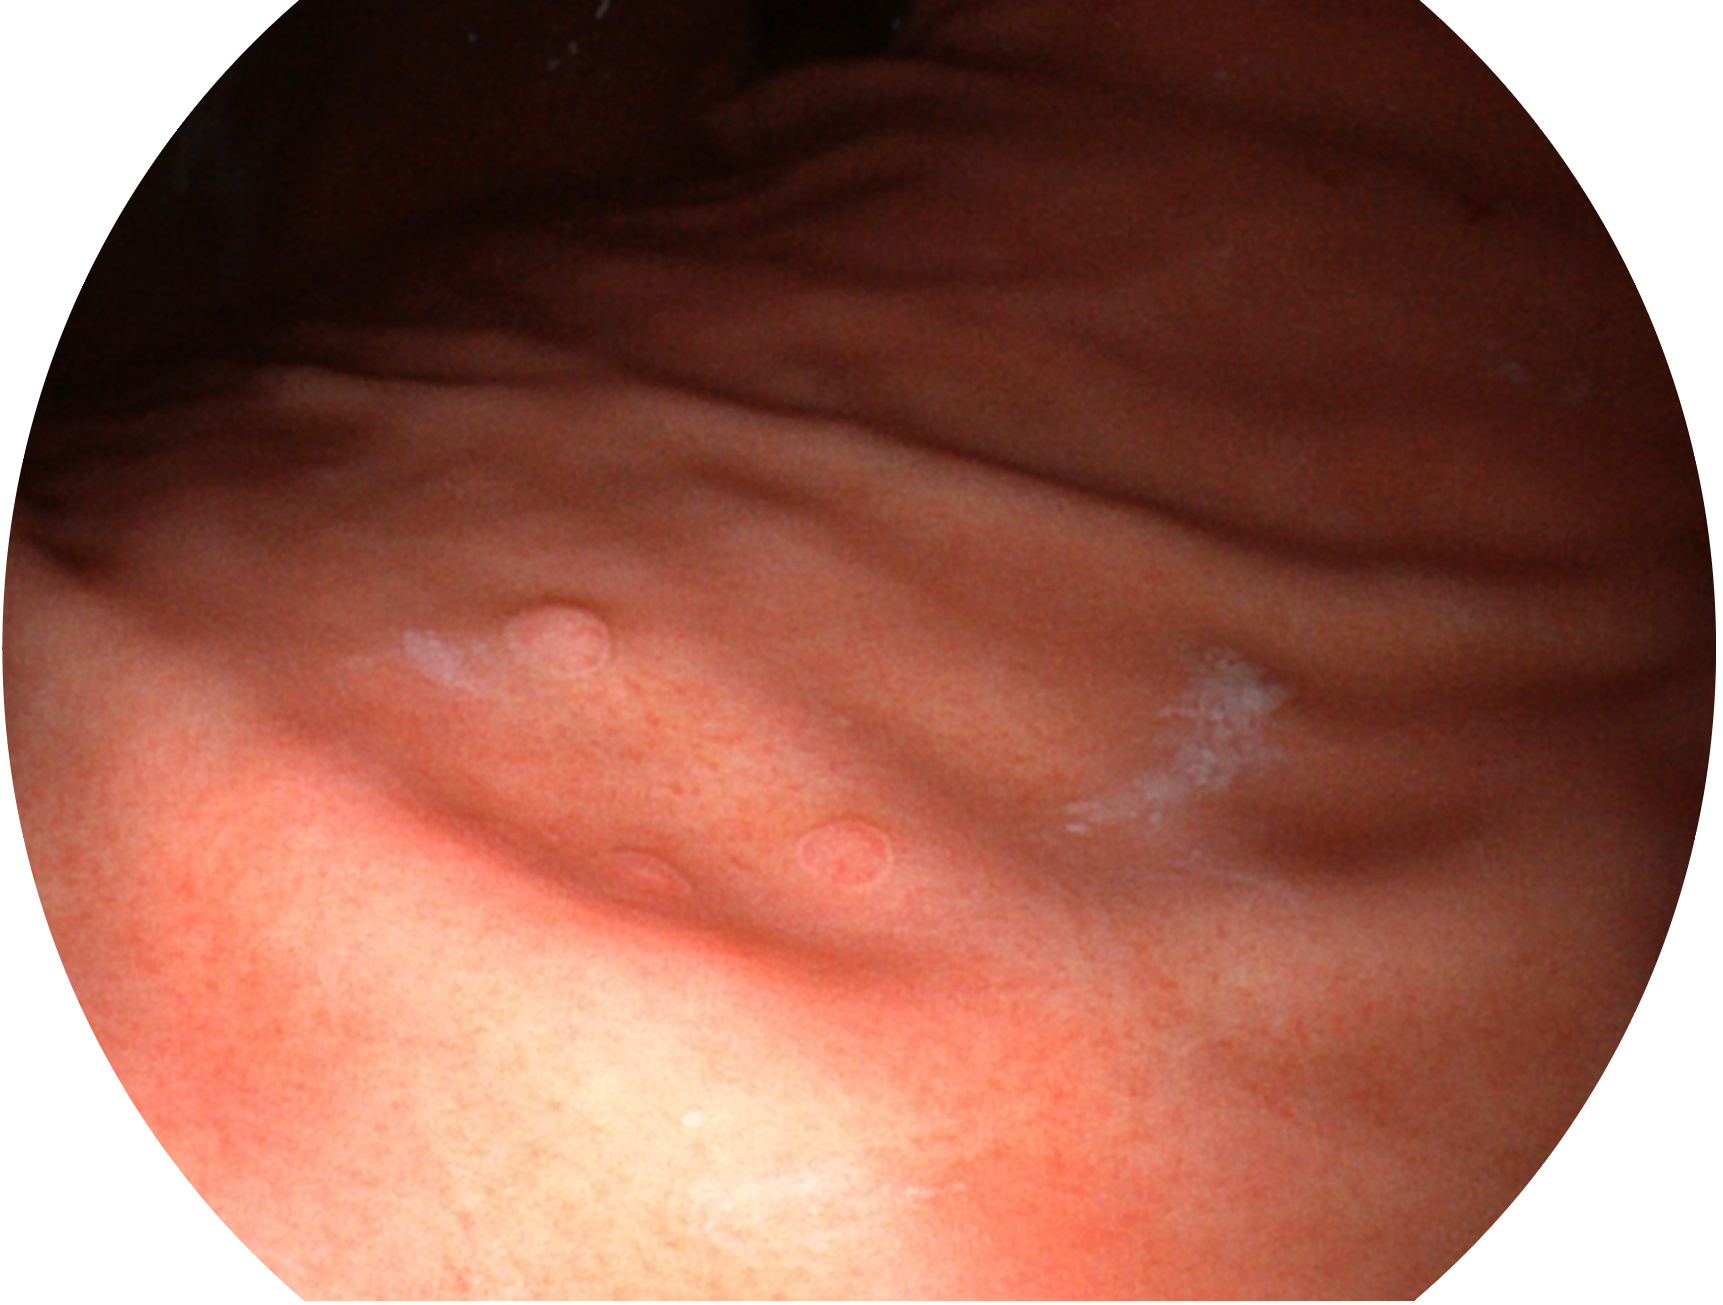

开立新开发的内镜染色技术,主要是基于多波长LED 光源的开发,VLS-55Q 四波长LED 光源是由四个不同颜色的LED光按照相应照明模式所规定的特定发光比例进行合束后形成,合束后形成的照明光的光谱由红光、绿光、蓝光及蓝紫光这四个不同的波段范围构成。具有更高光谱自由度,通过光谱比例的控制,实现了聚谱成像技术,英文全称为“Spectral Focused Imaging, SFI”,缩写为“SFI”和光电复合染色成像技术,英文全称为“Versatile Intelligent Staining Technology, VIST”,缩写为“VIST”。